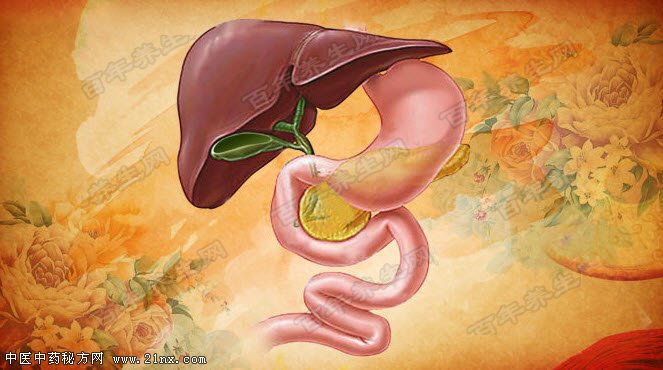

图:胆囊 胆囊出现结石、息肉、炎症时,究竟该不该切除胆囊?如果是高危类型的息肉,不积极切除胆囊,将可能有5%的癌变可能。 而胆囊虽小,但它与人体多个脏器交叉相连,一旦发生恶变,很容易累及肝脏、胰脏等,得不偿失,而切除胆囊,又会在一定程度上增加罹患结肠癌的风险。如果胆囊生病了,应该如何科学面对?